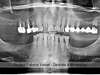

Panoramique visite de contrôle 06/2015

Visite de contrôle 06/2015